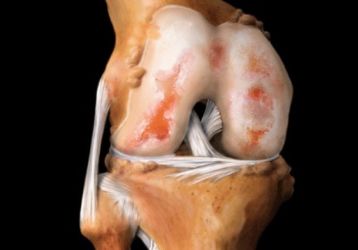

Что такое хондропатия коленного сустава: основные методы диагностики и лечения

Что представляет собой хондропатия коленного сустава: описание, виды, основные признаки и методы диагностики болезни. Способы лечения, последствия, прогноз.